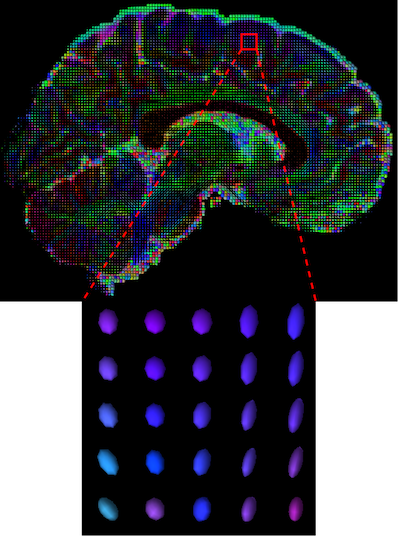

Diffusion Weighted Imaging (DWI) is a non-invasive magnetic resonance imaging (MRI) modality developed to monitor water diffusivity and reveal the micro-structure of the human body [1]. While conventional structural MRI sequences (e.g. T1, T2) provide information about the general morphological information of the brain, DWI provides additional information regarding brain dynamics with water diffusivity as a proxy. This set of sequences acquired with different gradient directions can then be summarised using a Diffusion Tensor Imaging (DTI) model to uncover microstructural information. Based on the fact that different tissues have different diffusion properties, the DTI model explains the directionality of the water diffusivity and its corresponding quantitative anisotropy [2]. The diffusion of a particular voxel can be characterized as an ellipsoid (Figure 1(a)) that can be mathematically formulated as a symmetric tensor matrix (Figure 1(b)). The coordinate system is typically aligned with the main magnetic field and body of the patient. Since the relationship between two principal directions is theoretically symmetric, i.e., , and , only 6 unique coefficients are needed to construct the tensor at a particular voxel.

The visualization of inpainted results (showing the whole diffusion tensor for each voxel) generated from different models are demonstrated in Figure 3, where the tensor is represented in RGB coding that colours red, green and blue represent diffusion in the x, y, and z axes respectively. One typical example of reconstruction in the disrupted ROIs has been zoomed for visualization. Compared to the ground truth, TW-BAG is able to generate more distinct orientations following the original distribution and intensity across sagittal, coronal and axial views, which could demonstrate water diffusivity (denoted by eigenvalues of tensor model) more accurately. As indicated in Figure 4, the boundaries and textures of the FA map for TW-BAG are less blurry than the other competing models, validating the effectiveness of TW-BAG from a neuroscience perspective.